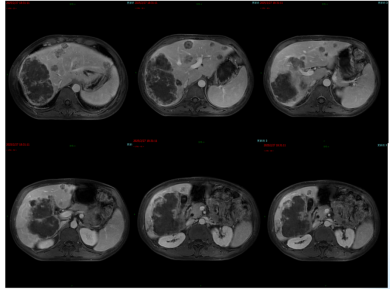

影像学检查:2024年7月30日,院外腹部CT显示乙状结肠管壁增厚,考虑肿瘤性病变(cT3N2,图1),2024年8月5日,肝脏MRI显示肝脏多发转移灶(侵犯门静脉右支、肝右静脉,图2)。2024年8月2日胸部CT显示双肺结节待排(图3)。

图2. 肝脏MRI

治疗4周期后,肝脏转移灶较基线缩小约20%(图5/6),CEA从532.4 ng/ml降至217.3 ng/ml,CA199从344.2 U/ml降至172.9 U/ml,评估为SD。

图5. 2024年10月24日CT:肝脏多发转移瘤,较大者位于右半肝,致肝右静脉、门静脉右支受侵

图6. 2024年10月29日MRI:肝脏多发转移瘤,伴有肝右静脉及门静脉右支受侵

肝脏病灶稍缩小(图8/9),评价为SD。但出现支架旁包裹性积气、积液,提示局部穿孔伴脓肿(图10)。

图8. 2024年12月27日CT:肝脏多发转移瘤,伴有肝右静脉及门静脉右支受侵,较2024年10月24日稍缩小

图9. 2024年12月29日MRI:肝脏多发转移瘤,伴有肝右静脉及门静脉右支受侵,较2024年10月24日稍缩小

图10. 2024年12月29日MRI:支架旁包裹性积气、积液,考虑局部穿孔伴脓肿形成可能

CEA、CA19-9略微升高(图17),肝脏多发转移瘤较前增多、增大(图15/16),双肺结节较前增多、增大(图14),评估为PD。

图14. 2025年2月25日CT:双肺结节,较2024年12月27日CT增多、增大

图15. 2025年2月25日MRI:肝脏多发转移瘤,较2024年12月29日MRI增多、增大

图16. 2025年2月25日MRI:术区未见异常强化影